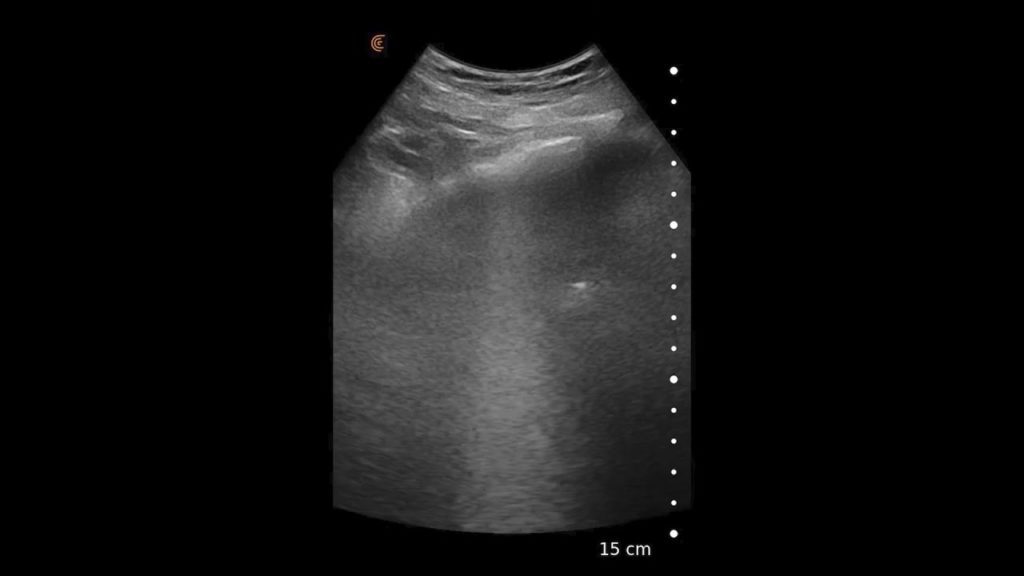

Using the jejunum as an important landmark, the hypoechoic jejunal lymph nodes can be identified. In this video Dr. Edwards explains the ultrasound appearance of normal jejunal nodes.